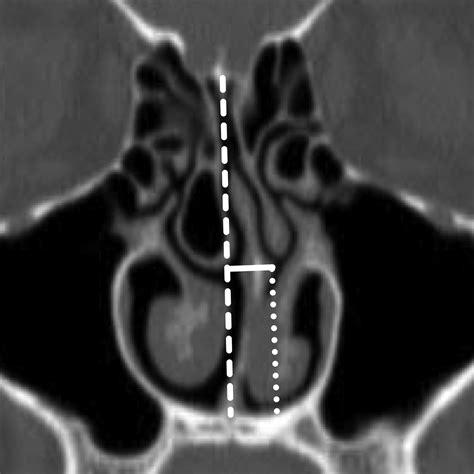

When an air cell develops within the middle turbinate, the structure expands significantly. This expansion is the defining characteristic of a Concha Bullosa. Depending on the size of the air pocket, the enlarged turbinate can press against the nasal septum or the lateral nasal wall, effectively narrowing the nasal passage and obstructing the narrow drainage pathways, known as the ostiomeatal complex, where the sinuses drain into the nose.

Diagnosing a Concha Bullosa typically requires more than a simple visual inspection during a physical exam. While an ENT might suspect the condition using an endoscope—a thin, flexible tube with a camera—a definitive diagnosis almost always relies on imaging. A Computed Tomography (CT) scan of the paranasal sinuses is the gold standard. It provides a detailed cross-sectional view of the nasal architecture, allowing the physician to measure the exact size of the air pocket and determine if it is contributing to sinus obstruction.

CT Scan Detailed imaging to confirm pneumatization and identify potential obstruction sites.